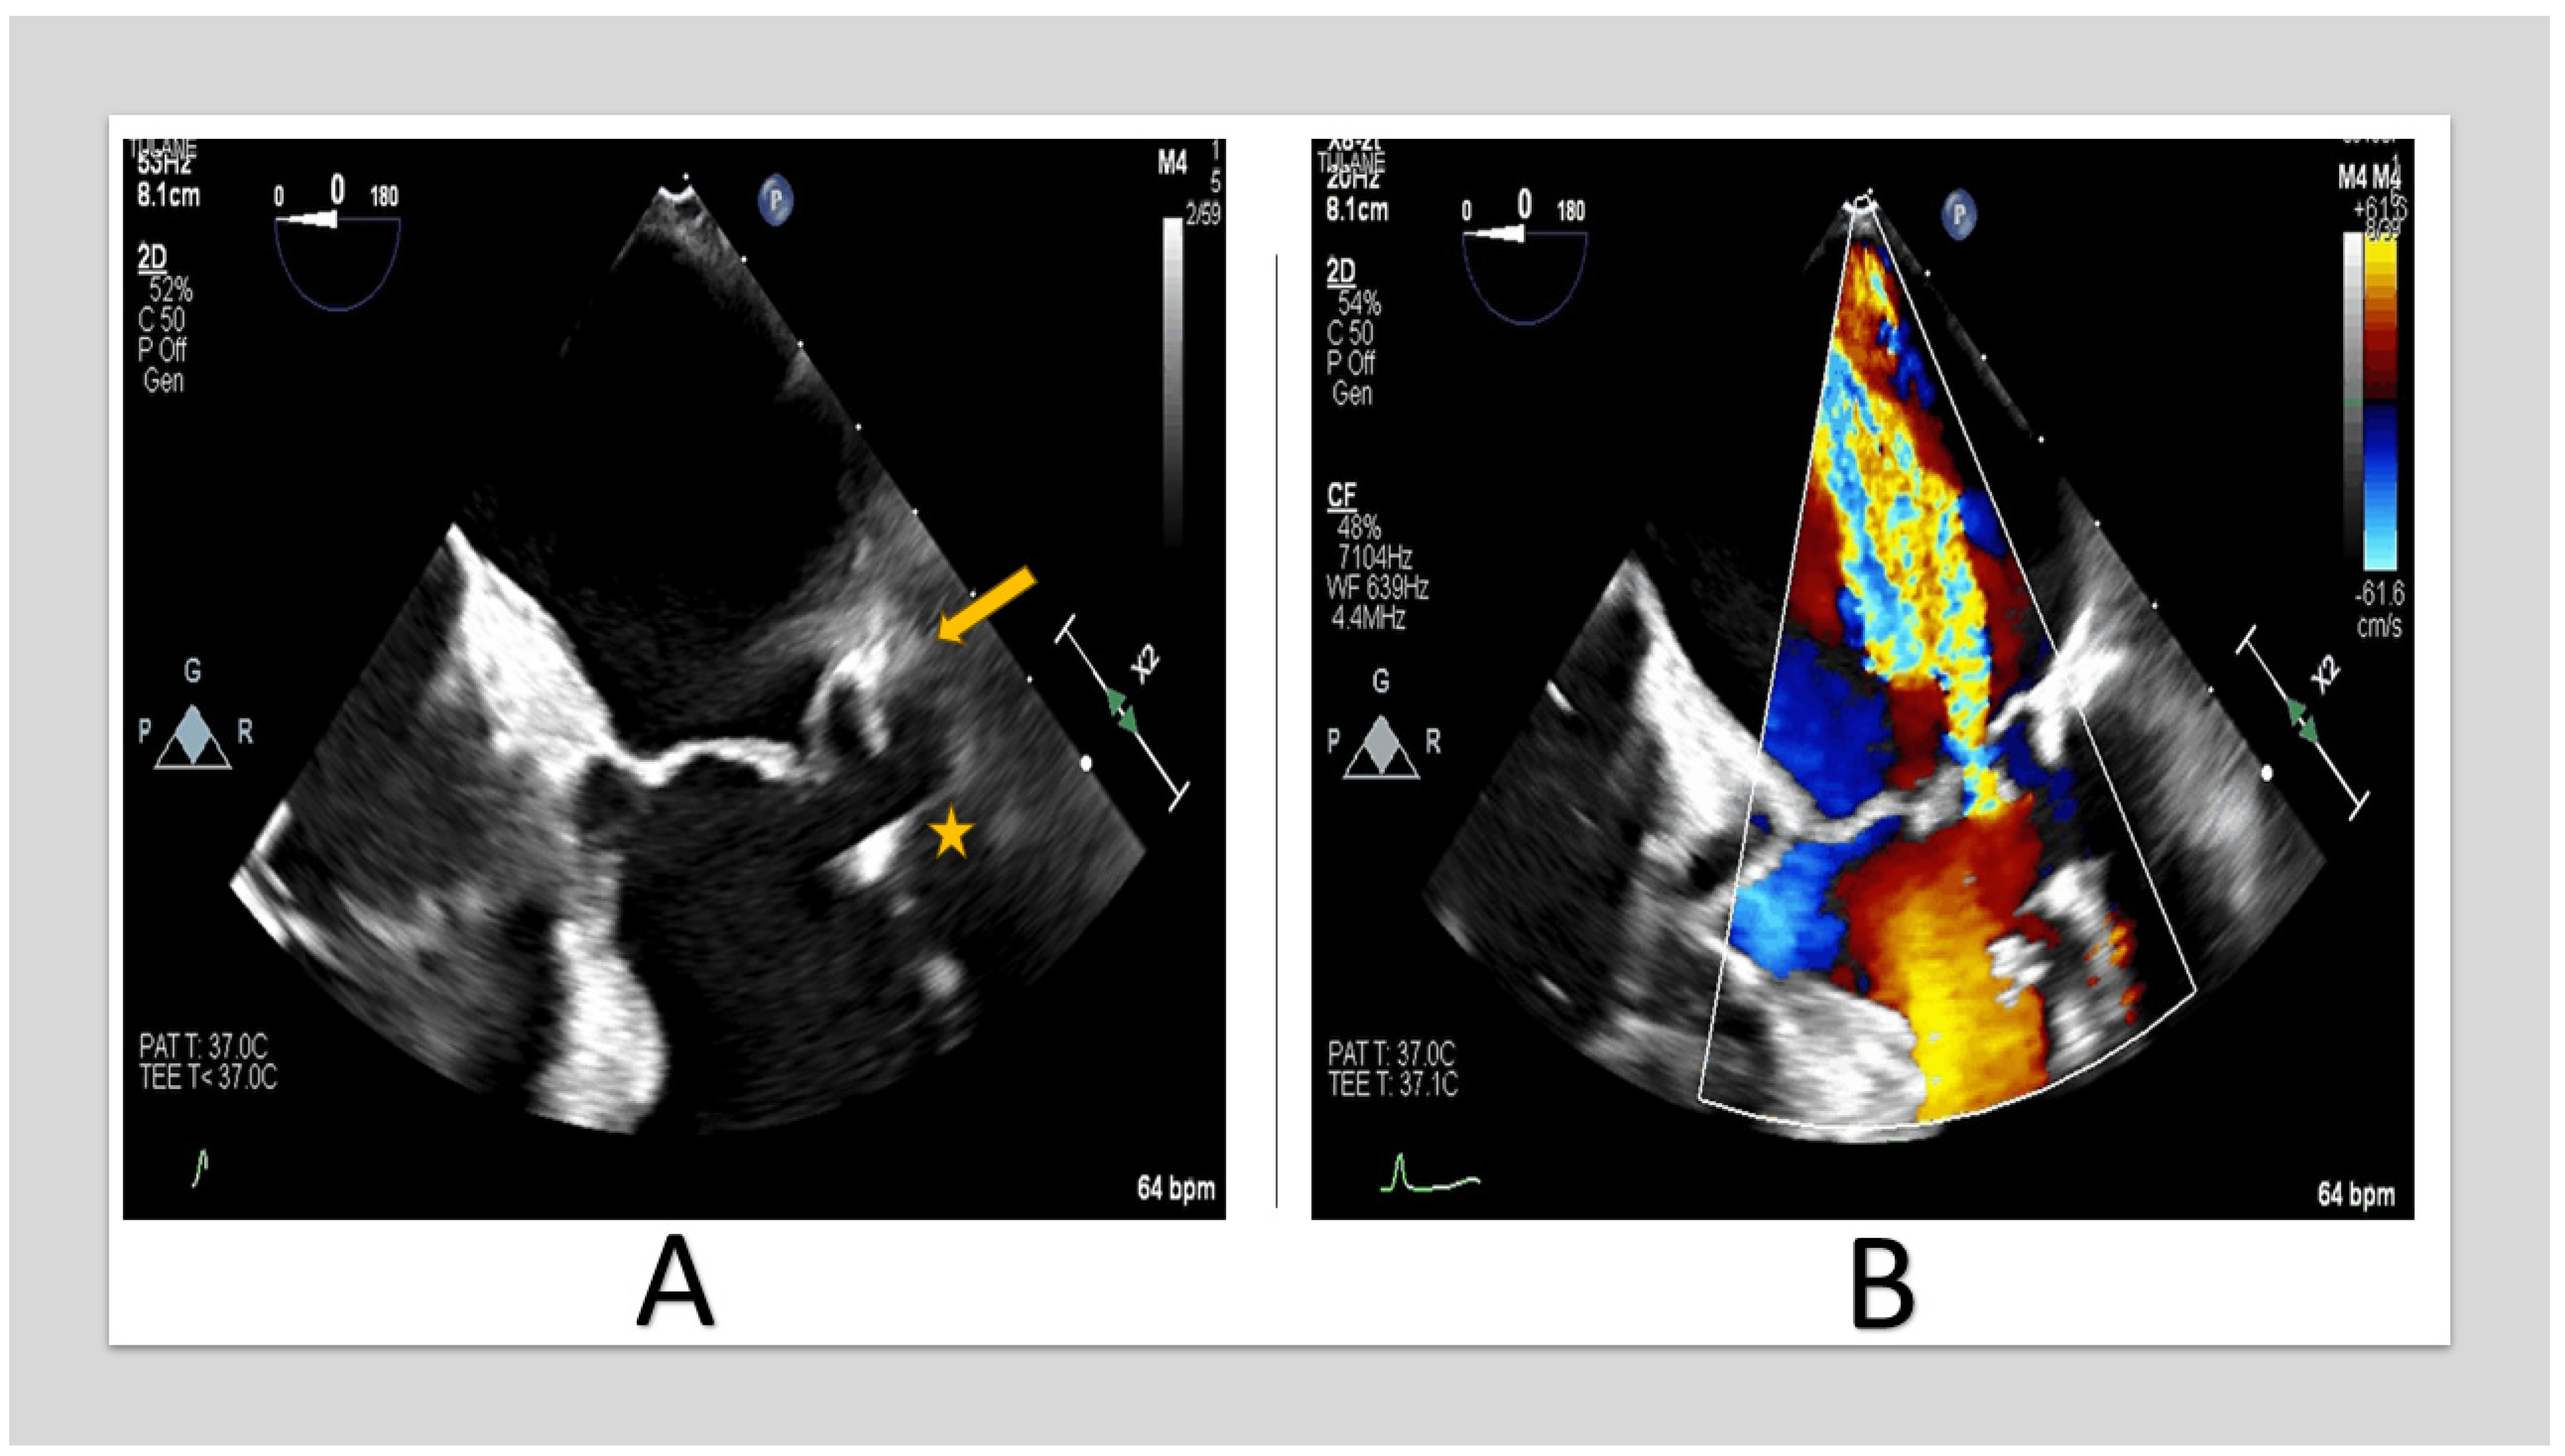

Extension of the posterior annulus calcifications to the posterior leaflet and sub-valvular apparatus resulting in restricted motion of the posterior leaflet and, therefore, lack of coaptation [21] (Figure 2).

TEE images of 67-year-old woman with severe MR. (A) shows posterior annulus calcification (arrow) with sub-valvular apparatus extension (star. (B) shows posteriorly directed MR jet due to posterior leaflet restriction. (TEE: transesophageal echocardiography, MR: mitral regurgitation).